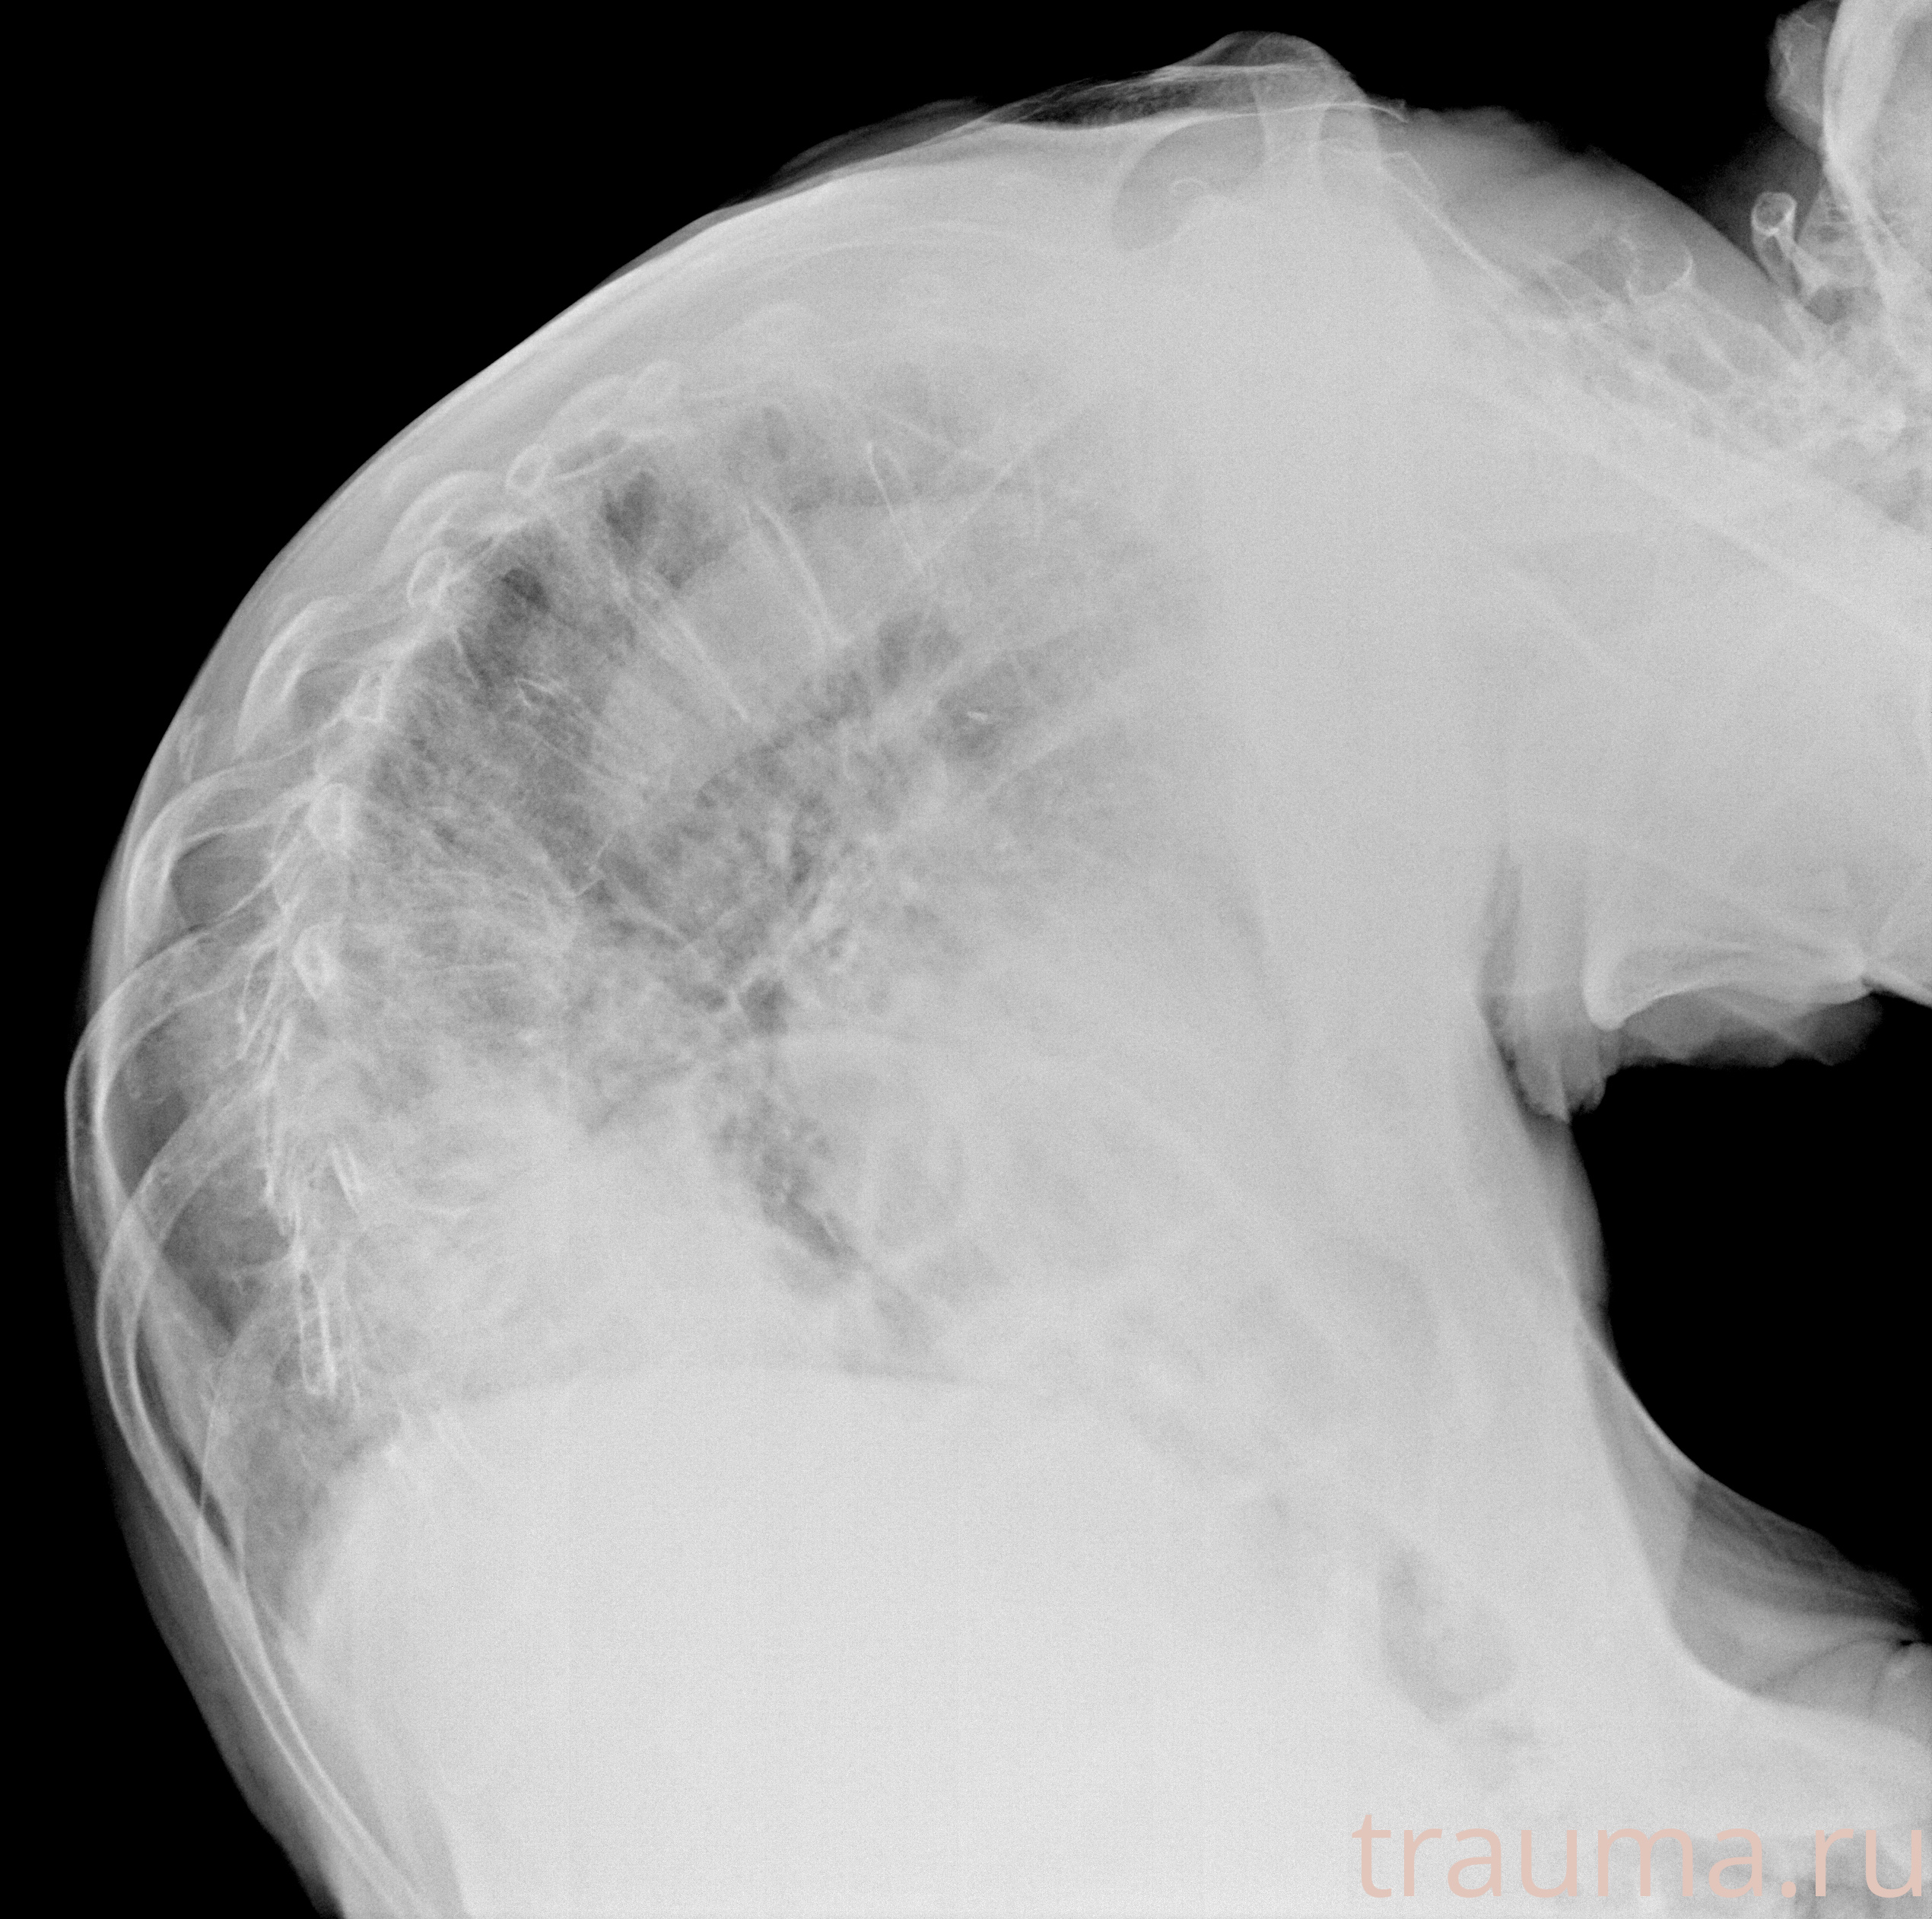

Рентген на дому: по вашему адресу приезжает врач-рентгенолог, травматолог-ортопед с мобильным рентгеновским аппаратом, проводит диагностику травмы или заболевания, делает необходимые рентгенограммы, дает рекомендации по дальнейшему лечению. Получить качественные снимки в домашних условиях возможно благодаря уникальной методике, разработанной МосРентген Центром для института  Склифосовского

при переломе шейки бедра и пневмонии от компании МосРентген Центр - партнера Института имени Склифосовского